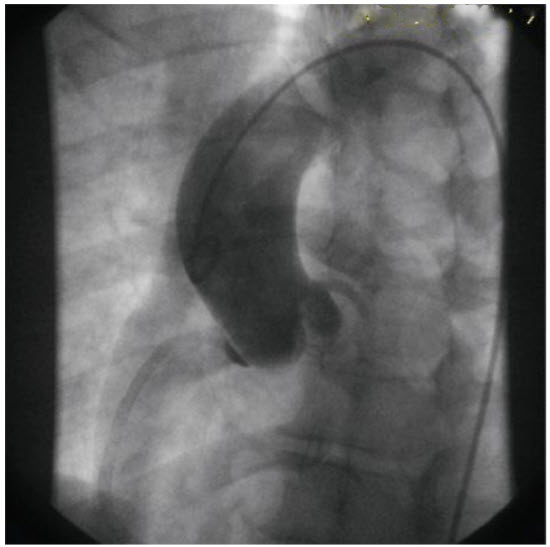

A 45-year-old woman with a history of fibromuscular dysplasia presents to the ER with an acute ST-elevation inferior MI. She is taken immediately to the cardiac catheterization laboratory for primary percutaneous intervention of the right coronary artery (RCA). The first injection of the RCA shows a dissection extending from the ostium to the posterior descending artery. A subsequent aortogram after stenting of the RCA is performed (figure below).

What does the aortogram show?

Aortic root localized dissection. Localized staining of contrast dye is seen in the region of the right sinus of Valsalva. This finding is consistent with an iatrogenic localized dissection. In this patient, it is likely due to either catheter trauma or retrograde propagation of the RCA dissection into the corresponding sinus of Valsalva. Coronary dissection is commonly associated with fibromuscular dysplasia. Contrast aortogram with staining of contrast seen in the right sinus of Valsalva that occurred post MI and following percutaneous coronary stenting in a young woman with fibromuscular dysplasia and RCA dissection. Contrast aortogram with staining of contrast seen in the right sinus of Valsalva that occurred post MI and following percutaneous coronary stenting in a young woman with fibromuscular dysplasia and RCA dissection (see figure in question).